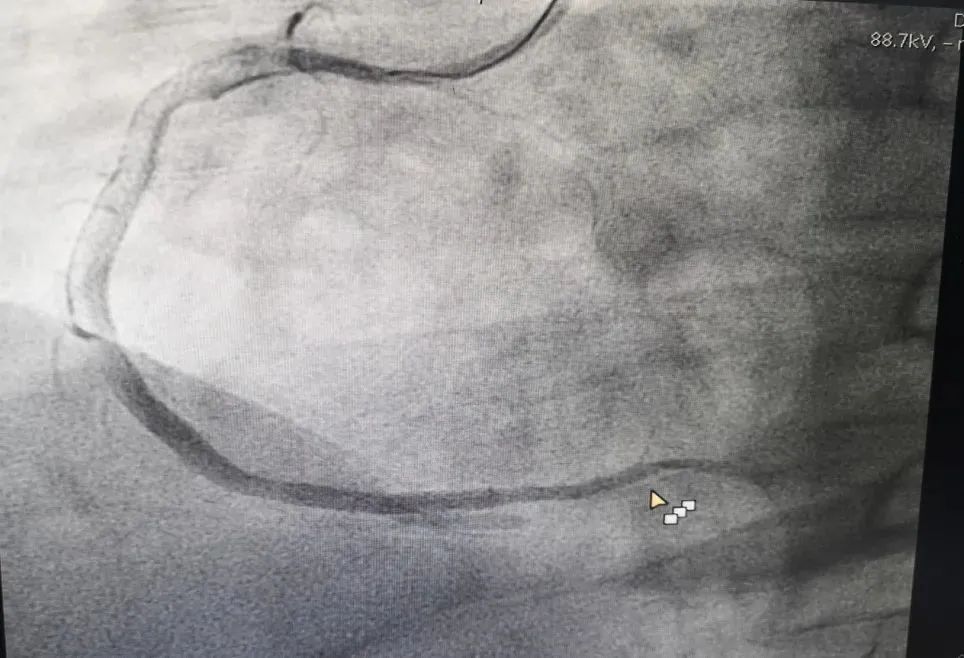

M老师在昏迷中,在各种仪器设备的强力生命支持条件下,由心血管介入团队对其完成了急诊冠脉造影检查——心脏右侧冠状动脉完全堵塞,伴有大量血栓形成。这是急性心肌梗死,需要马上手术开通血管。

心脏介入手术持续了差不多一个小时,从M老师一根堵塞的血管中抽出了大量新鲜血栓,并在严重狭窄的部位植入了两枚支架,整个血管恢复了良好的血流。  从堵塞的血管中抽出的新鲜血栓  血管开通后